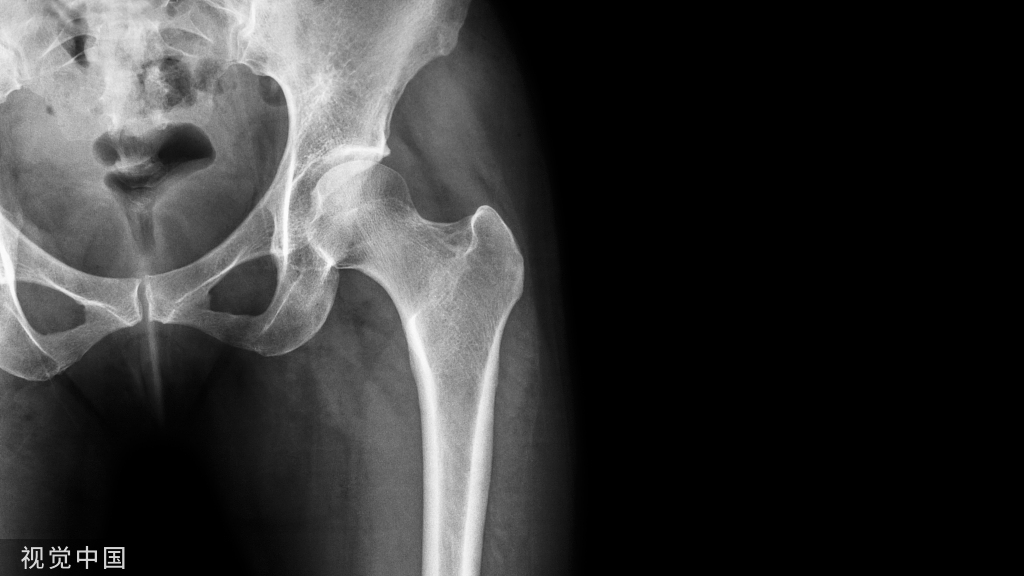

髌骨是我们膝盖前面的小小块骨头,他一般来说会顺着大腿骨(股骨)与小腿骨(胫骨)之间的轨迹行走。如果他今天失控跑出去撞到隔壁邻居的时候,就会产生磨损与疼痛,也就是髌股关节疼痛综合征。其实,大家的髌骨都很爱跑去撞外侧的邻居,髌骨去撞外侧邻居(股骨头)的现象称为髌骨外翻。